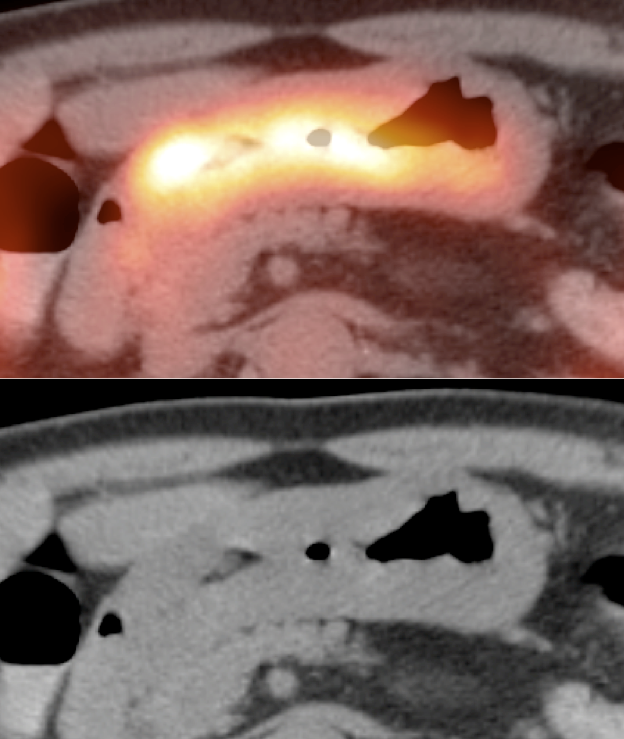

- Metformin-Induced Bowel Uptake